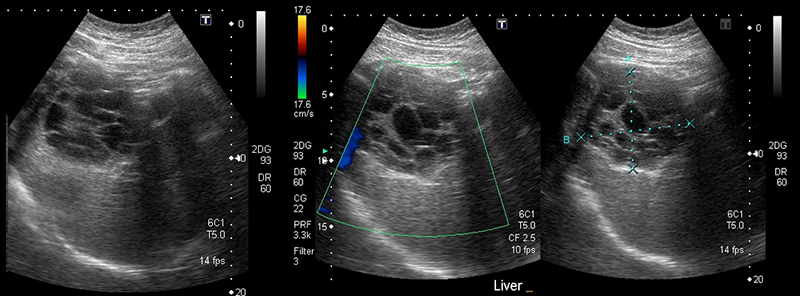

- Periportal fibrosis – thickening of the hyperechoic borders of the portal vein and branches.

Figure 54A. Transverse views of the liver revealing moderate periportal fibrosis. Note the thickened hyperechoic walls surrounding the portal vein and branches.

Figure 54B. Transverse views of the liver revealing moderate periportal fibrosis. Note the thickened hyperechoic walls surrounding the portal vein and branches.

- Portal hypertension

- Ascites

- Splenomegaly

- Dilated portal vein (>14mm)

- Reversal of portal venous flow by color Doppler

- Gallbladder wall thickening (>3mm)

- May see portal vein thrombosis